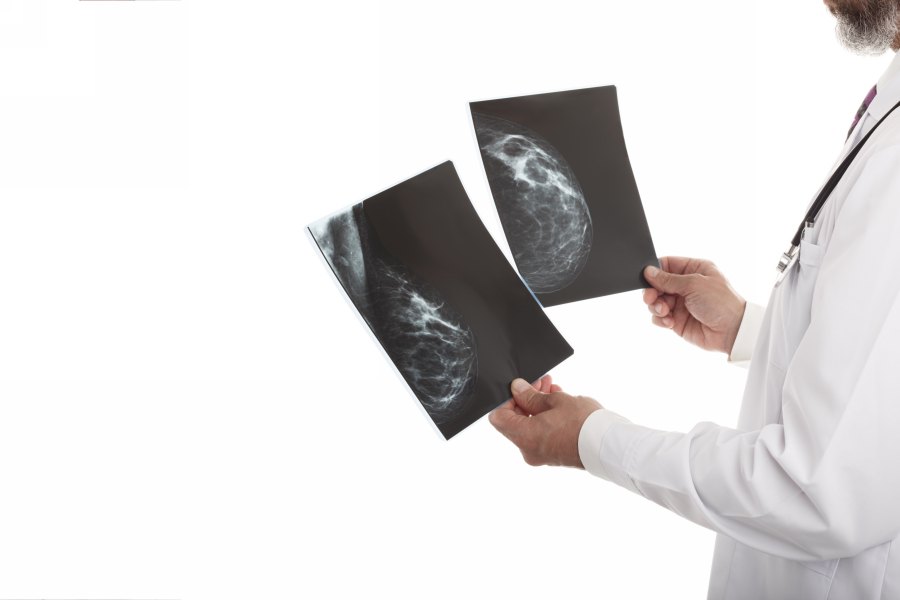

Маммография

Рентгенологическая маммография – скрининговый метод инструментальной диагностики молочной железы, который используется для определения аномальных бугорков, асимметрии и опухолей. Исследование определяет доброкачественные и злокачественные новообразования на начальных стадиях прогрессирования. Аномальный результат маммографического исследования необязательно указывает на раковый процесс, но требует проведения дополнительных анализов.

При стандартной процедуре снимки осуществляются в 2-х направлениях для каждой груди. Средняя чувствительность для выявления злокачественных опухолей составляет 79%, но у женщин с плотной структурой груди (много железистой и мало жировой ткани) способность метода определять опухоль иногда снижается в значительной степени.

Маммография по-прежнему остается информативным методом распознавания рака молочной железы. Методика дает возможность своевременно выявить даже незначительные изменения в 95-97% случаев. Диагностический метод является безопасным для обследуемых.

Маммография позволяет получить более точную картину. По результатам можно сказать, злокачественная или доброкачественная была обнаружена опухоль. Изображение четкое, видны патологические процессы в канале.

С помощью маммографии удается поставить точный диагноз и определить стадию патологического процесса в организме. Низкие дозы излучения улавливают любые изменения, связанные с плотностью тканей. Диагностика с внутривенным введением контрастного вещества способствует визуализации патологического увеличения сосудов вокруг атипичных очагов, что является признаком опасного вида новообразований.